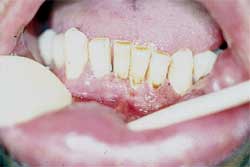

Acude a la consulta del Servicio de Clínica Estomatológica de la Facultad de Odontología de la Universidad Central de Venezuela, un paciente masculino de 40 años de edad, natural y procedente de Caracas, por presentar lesiones granulomatosas en la cavidad bucal, de aproximadamente un año de evolución. Al examen clínico extrabucal se observa edema del labio inferior y pueden palparse ganglios no dolorosos en la cadena cervical y yugulo-digástrica, llama la atención la voz nasal del paciente. Al examen clínico intrabucal se observan varias lesiones granulomatosas en encía antero inferior, cara interna del labio inferior y cara interna del carrillo derecho, ésta lesiones exhibían un aspecto infiltrante con puntillado eritematoso, de consistencia firme, dolorosas a la palpación y a la masticación de los alimentos. Las lesiones de la encía antero-inferior mostraban un puntillado más eritematoso.

Fig.1 cavidad bucal